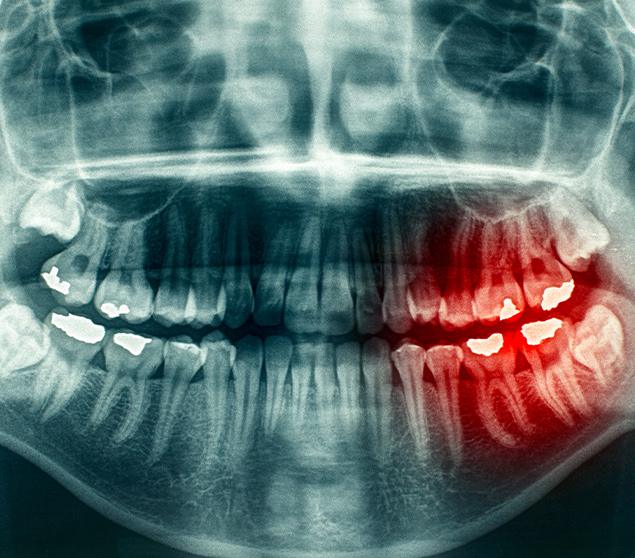

Digital X-ray systems allow images to be viewed quickly on screen and shared with patients during their visit. This helps support clear communication and understanding of findings.

Compared to traditional film X-rays, digital systems typically require lower radiation exposure and eliminate the need for chemical processing. Images are stored securely in your dental record and can be compared over time to monitor changes.